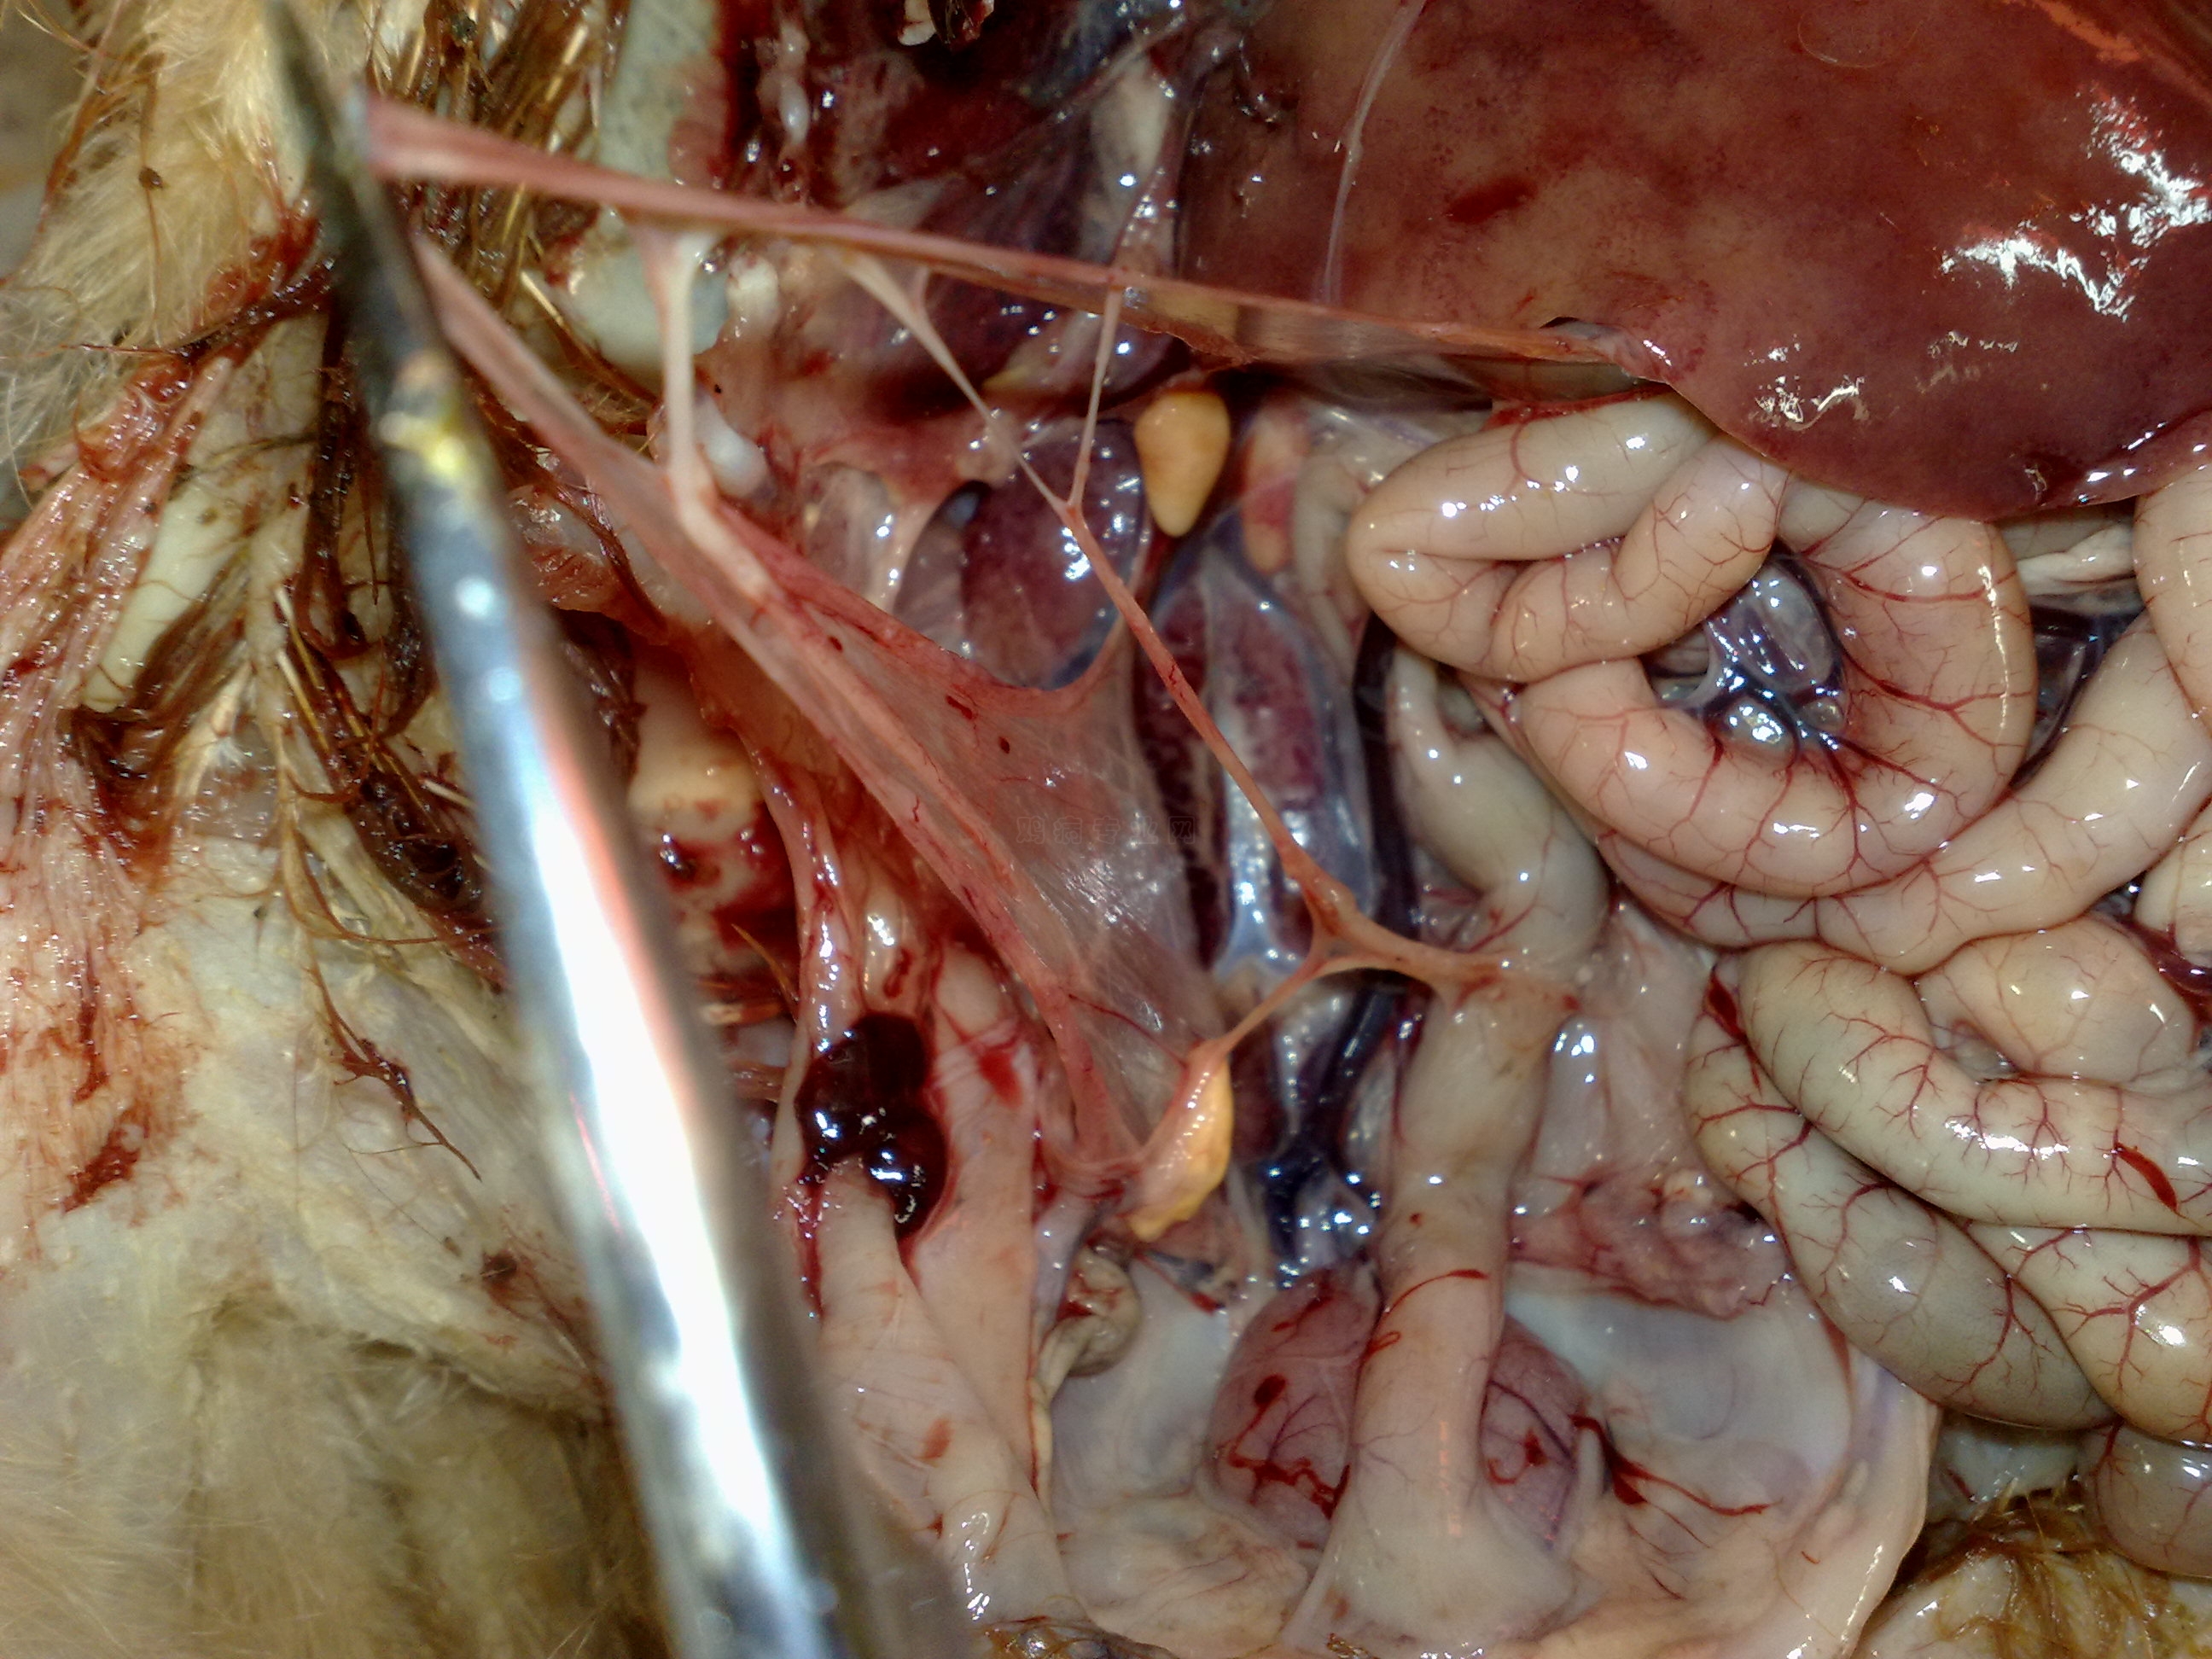

我的鸡5000只已经75天了,咳嗽将近30天了,但是鸡只大群采食量正常,晚上进鸡舍后休息时就听到咳嗽,呼噜,怪叫等呼吸道症状,鸡只死亡率低,解剖盲肠扁桃体有病毒,气囊浑浊,喉头有粘液气管严重充血,先后西药用过强力霉素,阿奇霉素,氟苯尼考,泰乐菌素,力高霉素,利巴韦林。中药用麻黄,板蓝根,鱼腥草,黄芪,黄连,防风,党参,甘草等等熬水喂服。甚至我还紧急注射传支传喉卵黄抗体可是效果都不是很理想。我要崩溃了,求各位前辈高人指点,小弟感恩戴德.555555555555555请问各位高手这是什么病啊,我就要崩溃了....

你的鸡主要是非典型新城疫和法氏囊。这个图片就是法氏囊

这个图片就是法氏囊病鸡的粪便

另外,由于你长期用药,已经使肠道的菌群平衡失调,厌氧菌已经发作。

治疗建议:使用治疗新城疫和法氏囊的药物+头孢噻肟钠+甲硝唑。即可治愈。

以上三个图片,气管出血没有明显的分界线,是非典型新城疫。